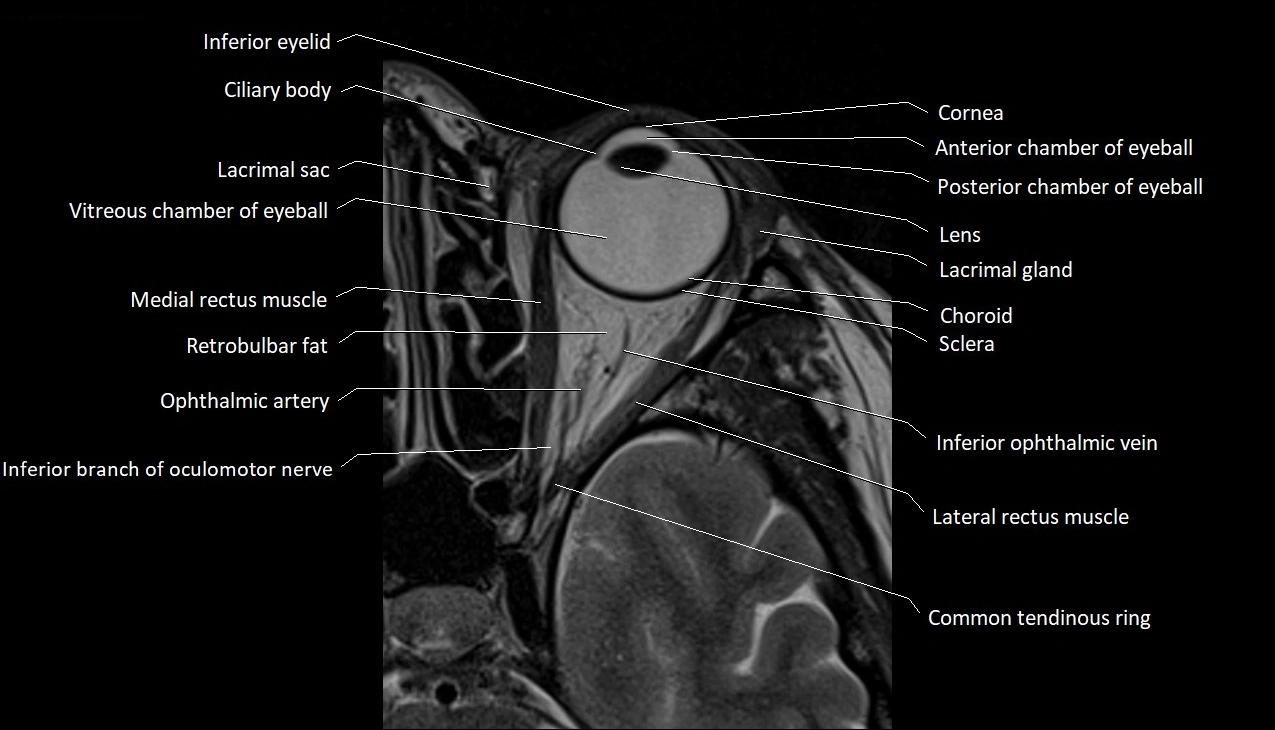

- Anterior chamber of eyeball

- Choroid

- Common tendinous ring (Annulus of zinn)

- Cornea

- Inferior ophthalmic vein

- Lacrimal gland

- Lateral rectus muscle

- Medial rectus muscle

- Posterior chamber of eyeball

- Retrobulbar fat

- Sclera

- Vitreous chamber of eyeball

- lens of the eye